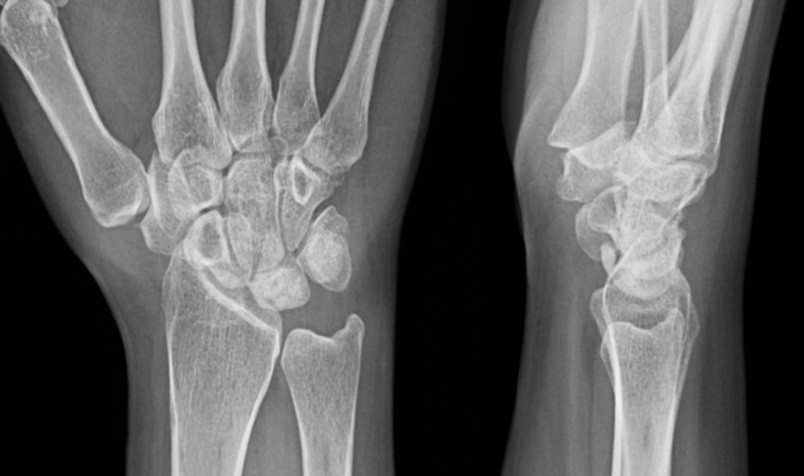

The mean follow-up duration was 24 months (Patient A: 36 months and Patient B: 12 months). Bone consolidation of the radial osteotomy was achieved on average 3 months postoperatively for both patients, while consolidation of the lunate fracture occurred at 6 months for Patient A (Fig. 9) and at 7 months for Patient B (Fig. 10). Lunate fracture union and radial osteotomy union were assessed with CT.

Figure 9: Patient A – X-ray and computed tomography scan: radius/ lunate consolidation.

Figure 10: Patient B X-ray and computed tomography scan: radius/ lunate consolidation.

CT was chosen because it is widely regarded as more reliable than radiographs for assessing carpal bone union and arthrodesis/osteotomy healing, and is appropriate when the clinical course is favorable. Routine post-operative perfusion studies were not pursued because the clinical evolution was satisfactory, and structural union had been demonstrated on CT.